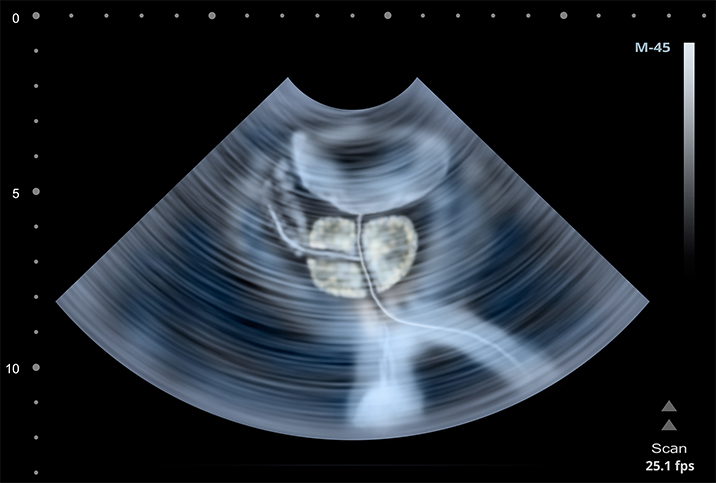

This natural enlargement of the prostate isn't cancerous but may cause uncomfortable symptoms.